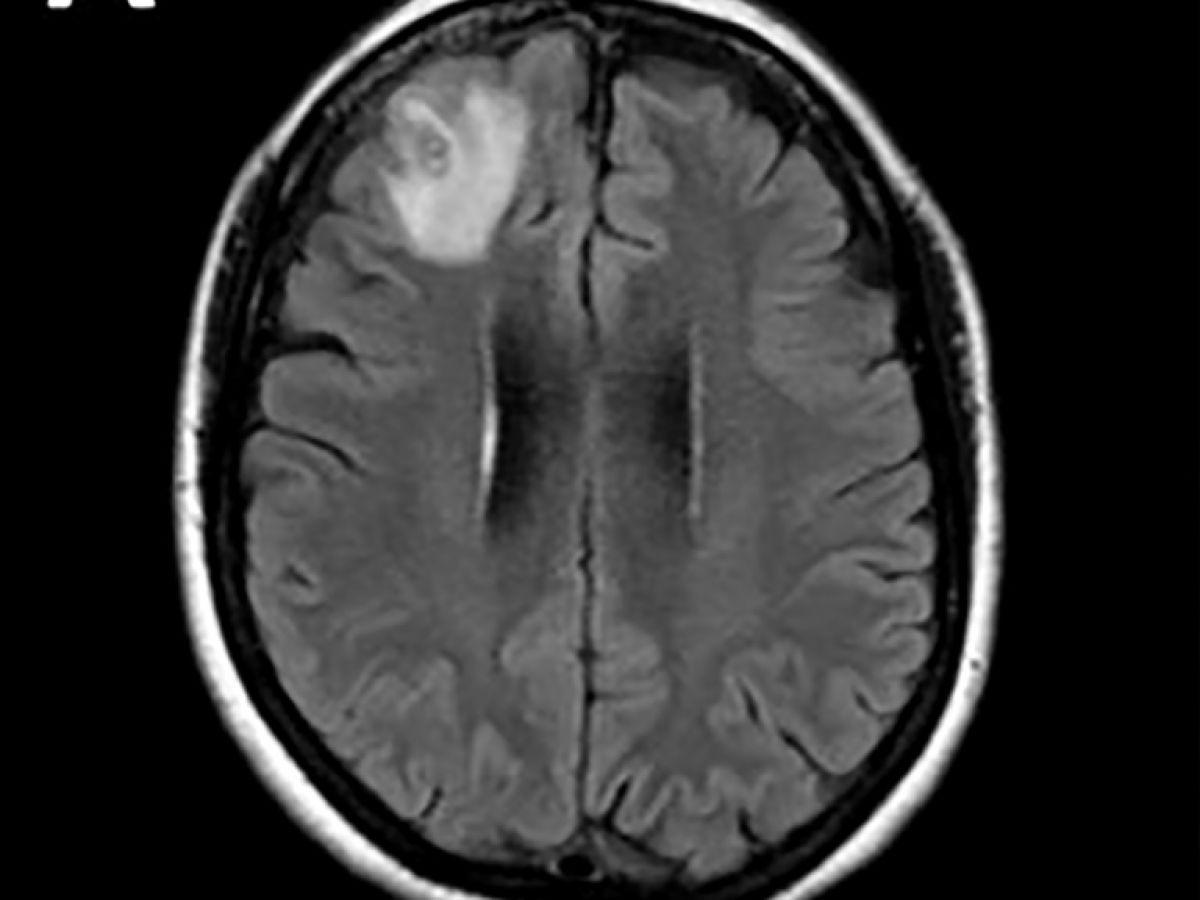

Africa-Press – Mali. Un ver rond, qui parasite généralement les serpents, a été découvert pour la première fois sur un être humain. Il a été extrait “vivant et se tortillant” du cerveau d’une Australienne lors d’une intervention chirurgicale, ont annoncé mardi des médecins australiens. Les médecins ont découvert une “lésion atypique”, grâce à un examen IRM, dans la partie frontale du cerveau de cette femme âgée de 64 ans qui souffrait de pertes de mémoire.

“À notre connaissance, c’est également le premier cas impliquant le cerveau d’une espèce de mammifère, humaine ou autre”, a-t-il précisé. Cette découverte a fait l’objet d’un article dans la revue “Emerging Infectious Diseases”. Les scientifiques pensent que l’Australienne a été parasitée par des plantes comestibles, probablement contaminées par des larves présentes dans des excréments de serpents. Le parasite, dont la “structure en forme de fil” est apparue sur les scanners cérébraux, a ensuite été identifié grâce à des tests ADN. “Il n’est jamais facile ni souhaitable d’être le premier à être malade de quoi que ce soit au monde”, a ajouté le Dr Senanayake, “je ne saurais trop exprimer notre admiration pour cette femme, qui a fait preuve de patience et de courage tout au long de ce processus.” Selon le Dr Senanayake, il est “probable que d’autres cas soient identifiés à l’avenir”.